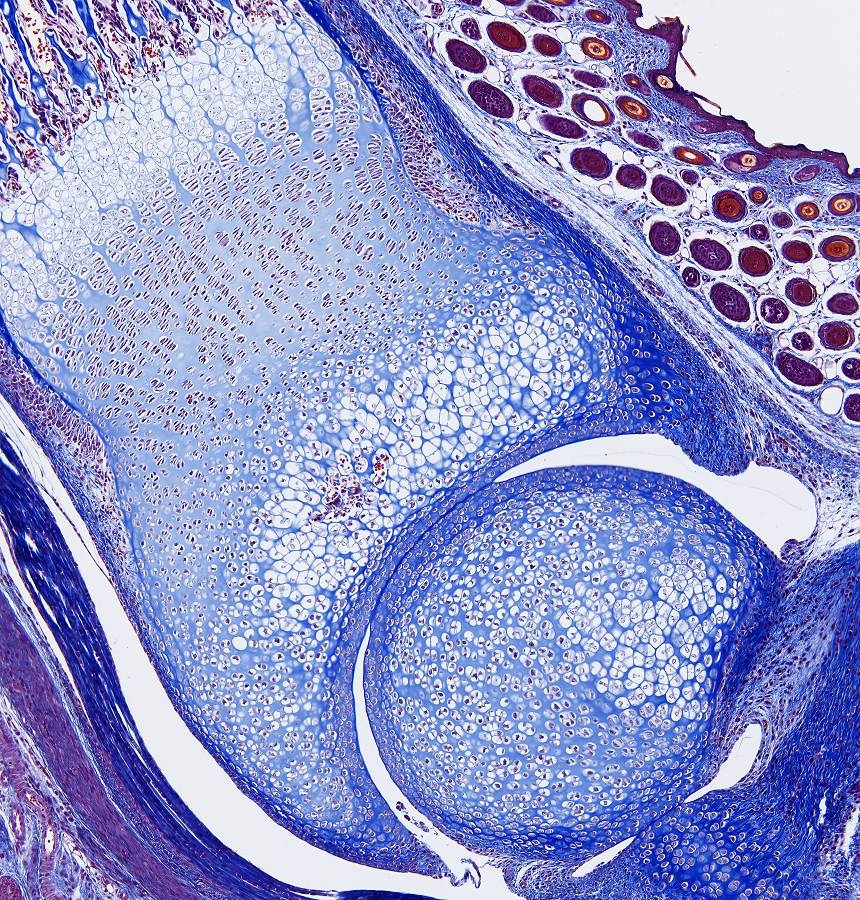

Chondrale Ossifikation,

Das Besondere der chondralen Knochenbildung ist, dass das zukünftige Skelettelement zuerst knorpelig angelegt wird. Dieses Knorpelstuck wird dann in einem komplexen Prozess abgebaut und durch Knochengewebe ersetzt (indirekte Knochenbildung). Durch dies en Mechanismus entstehen die meisten Knochen des Körpers, z. B. die Extremitätenknochen und die Wirbel.

Knorpel-Knochen-Grenze Im wachsenden verknöchernden Skelettstück lasst die Knorpel-Knochen-Grenze einen regelhaften Aufbau erkennen.

• Der Knorpel der (noch) nicht verknöcherten Epiphyse ist fetaler Knorpel.

• In Richtung auf die Verknöcherungszone folgt dann der Säulenknorpel, in dem die Knorpelzellen proliferieren und sich in Reihen (Säulen) anordnen; diese Knorpelzellen sind oft etwas abgeflacht.

• Es folgt dann die Zone des Blasenknorpels mit seinen großen mitochondrienreichen ("hypertrophen") Zellen, in deren Umgebung die Knorpelmatrix verkalkt.

• Es folgt die Eröffnungszone, die Front zur Zone der Knochenbildung, an der die Knorpelzellen abgebaut und die Knorpelhohlen sowie die spießartig dazwischenliegende verkalkte Knorpelmatrix von Osteoblasten besiedelt werden, die mit der Abscheidung von Knochenmatrix beginnen.

• Der Eröffnungszone, in der auch die meisten Chondroklasten zu finden sind, schließt sich dann die sehr gefaßreiche Zone mit Knochenbälkchen an, die hier oft noch Reste verkalkter Knorpelmatrix enthalten und an denen auch schon Osteoklasten auftreten, als Zeichen für schon sofort beginnende Umbauvorgange.

Knorpel = Leichtblau;

Knochen = Dunkelblau;

Stitch von 12 Bilder mit ein 16x Plan Fluotar Objektiv.

Blaue Band ist die Achillessehne, daneben ein grossen Längs geschnittene Nerv.